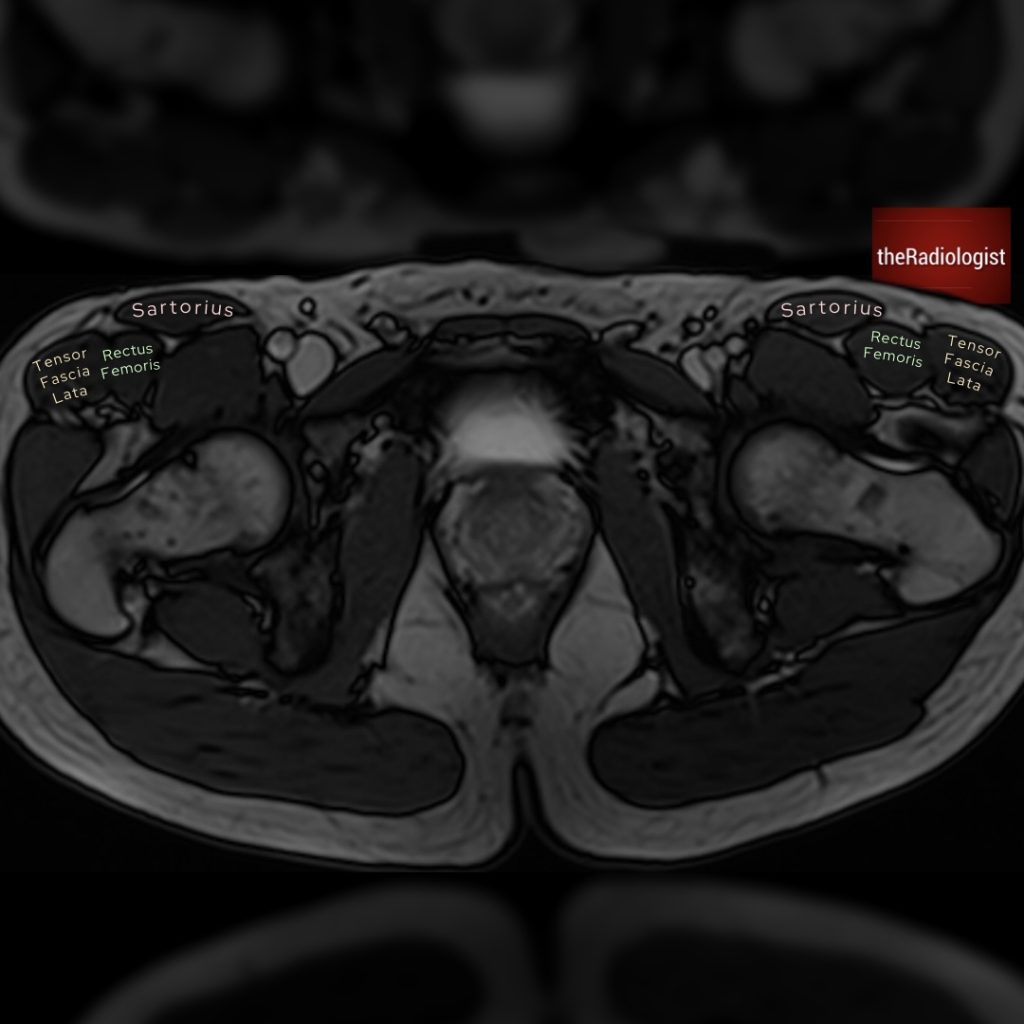

Case 6

Another MRI, this time we’re going down to the pelvis. What is the arrow pointing at?

Choose from one of the following options: